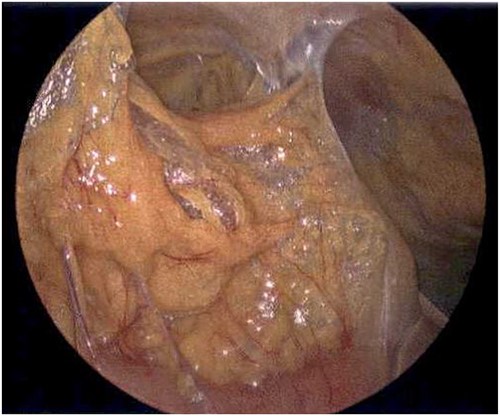

On Hospital Day 2, an interval CXR showed continued resolution of the right-sided pneumothorax but worsening subcutaneous emphysema of the bilateral chest wall and pneumoperitoneum (Fig. 3). Surgical consultation was sought, leading to diagnostic laparoscopy. In the abdomen, emphysematous changes within the gastrohepatic ligament and omental adhesions to the anterior abdominal wall were visualized (Figs 5 and 6). Laparoscopic exploration revealed no diaphragmatic injury or perforated viscera but identified emphysematous changes throughout the preperitoneal space, small and large bowel mesentery, and right paracolic gutter (Figs 7 and 8). Immediate post-op CXR no longer showed evidence of pneumoperitoneum (Fig. 4). The patient was transferred back to the ICU and extubated after three days on Day 5. After the removal of chest tube and transfer to a medical floor on Day 8, the patient developed aspiration pneumonia that was treated with antibiotics. She was discharged on Day 15.

Laparoscope of the right paracolic gutter revealing emphysematous changes of the mesentery.